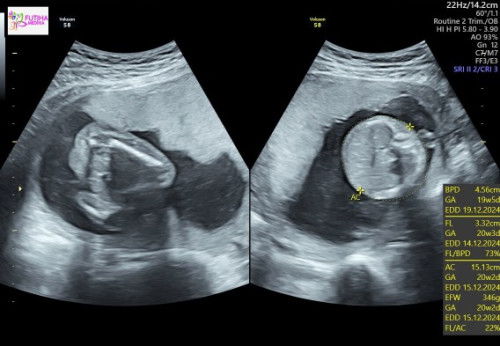

Hamil 2 bln perut terasa keram

Mau tanya bund, saat ini usia kandungan saya kan 8week2days atau 2bln. Kadang suka merasa keram perut, terus kalau tidur terlentang suka ngap gtu, kalau posisi samping suka agak (kagok) ada rasa nyeletit2 di perut gtu apalagi kalau tengkurep kadang ada rasa ngilu kalau keteken, itu wajar ga bun? Makasih bunda mohon bantu jawab, soalnya ini kehamlian pertama sya🥰#SeriusTanya #Sharing_dong_Bund #bantujawab #ingintahu